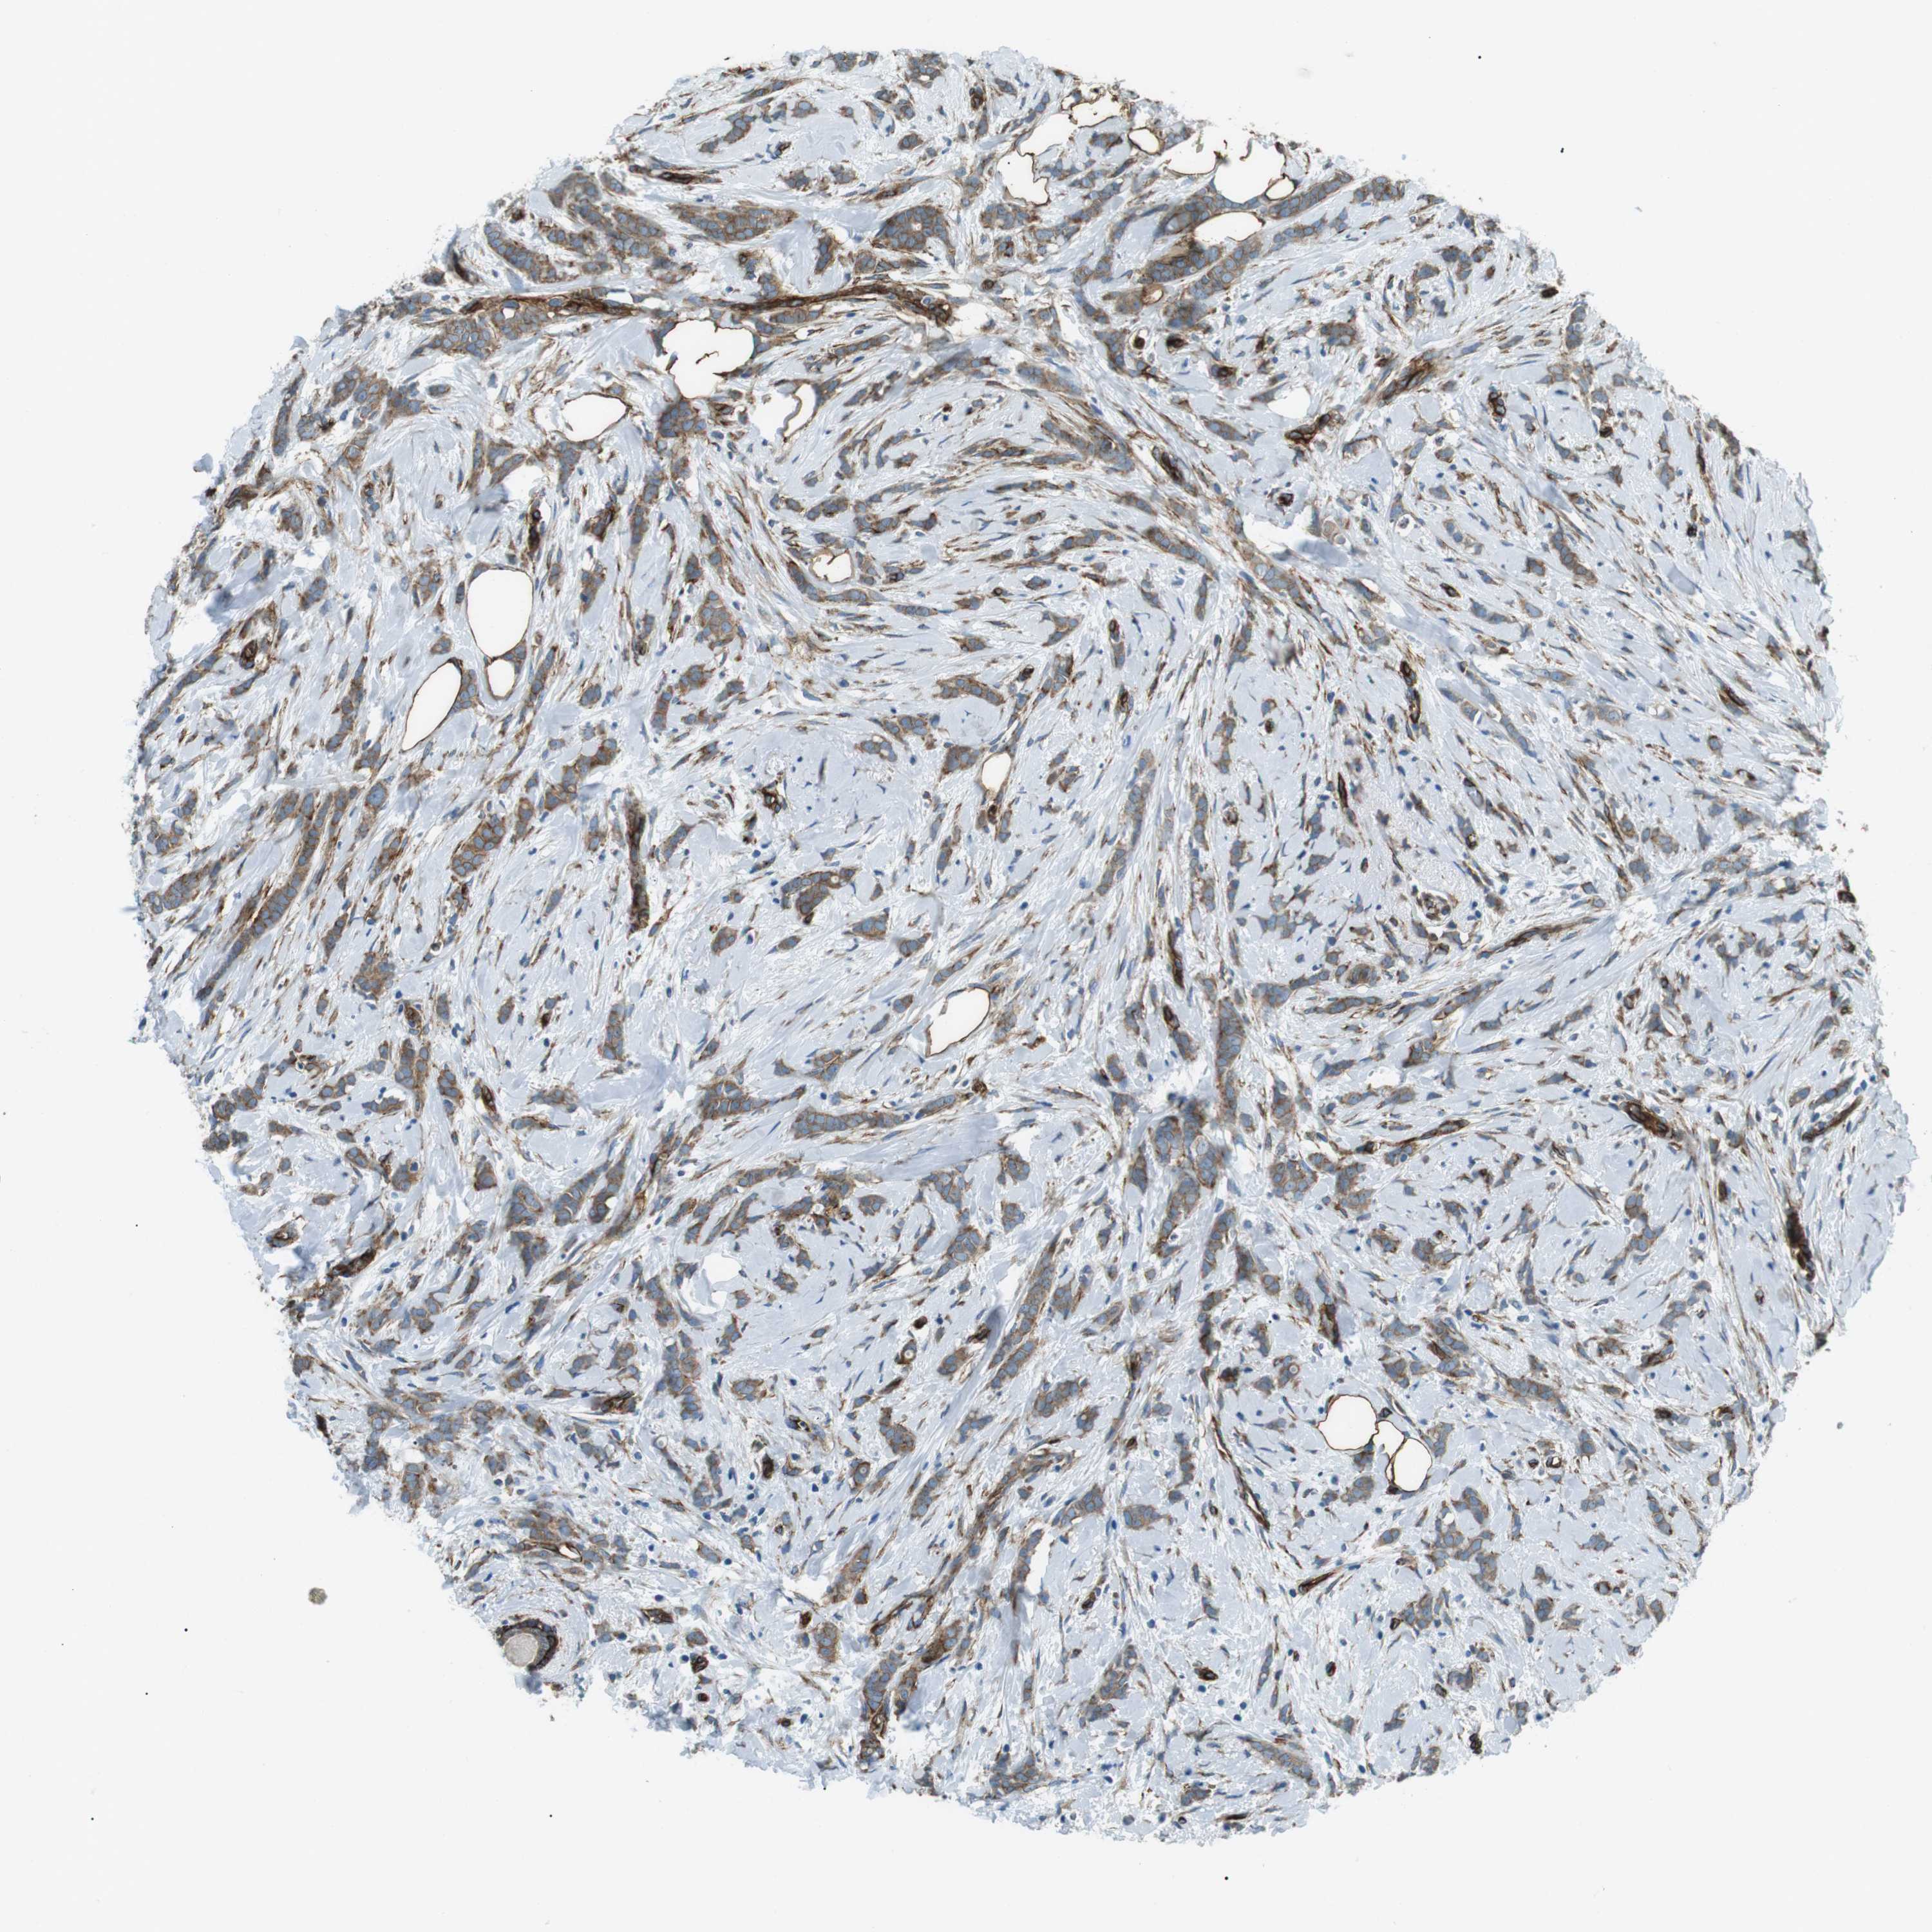

BRCA TCGA BRCA VALIDATION PROTEIN EXPRESSION

ANTIBODIES

AND

VALIDATION